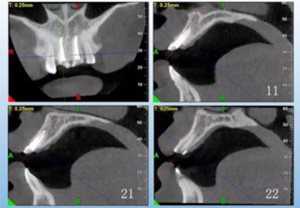

患者,女性,23歲,外傷導(dǎo)致上前牙折斷3天。檢查:中微笑 線;上頜右側(cè)中切牙至左側(cè)側(cè)切牙殘根,不松動,腭側(cè)缺損達齦下5mm, 牙齦中等厚度,齦緣基本完好。CBCT顯示:根長約11mm,牙根長軸與牙 槽突方向基本一致,唇側(cè)骨板完好、厚度1.0mm,可用骨高度21mm。全身情況良好。

圖3 術(shù)前CBCT